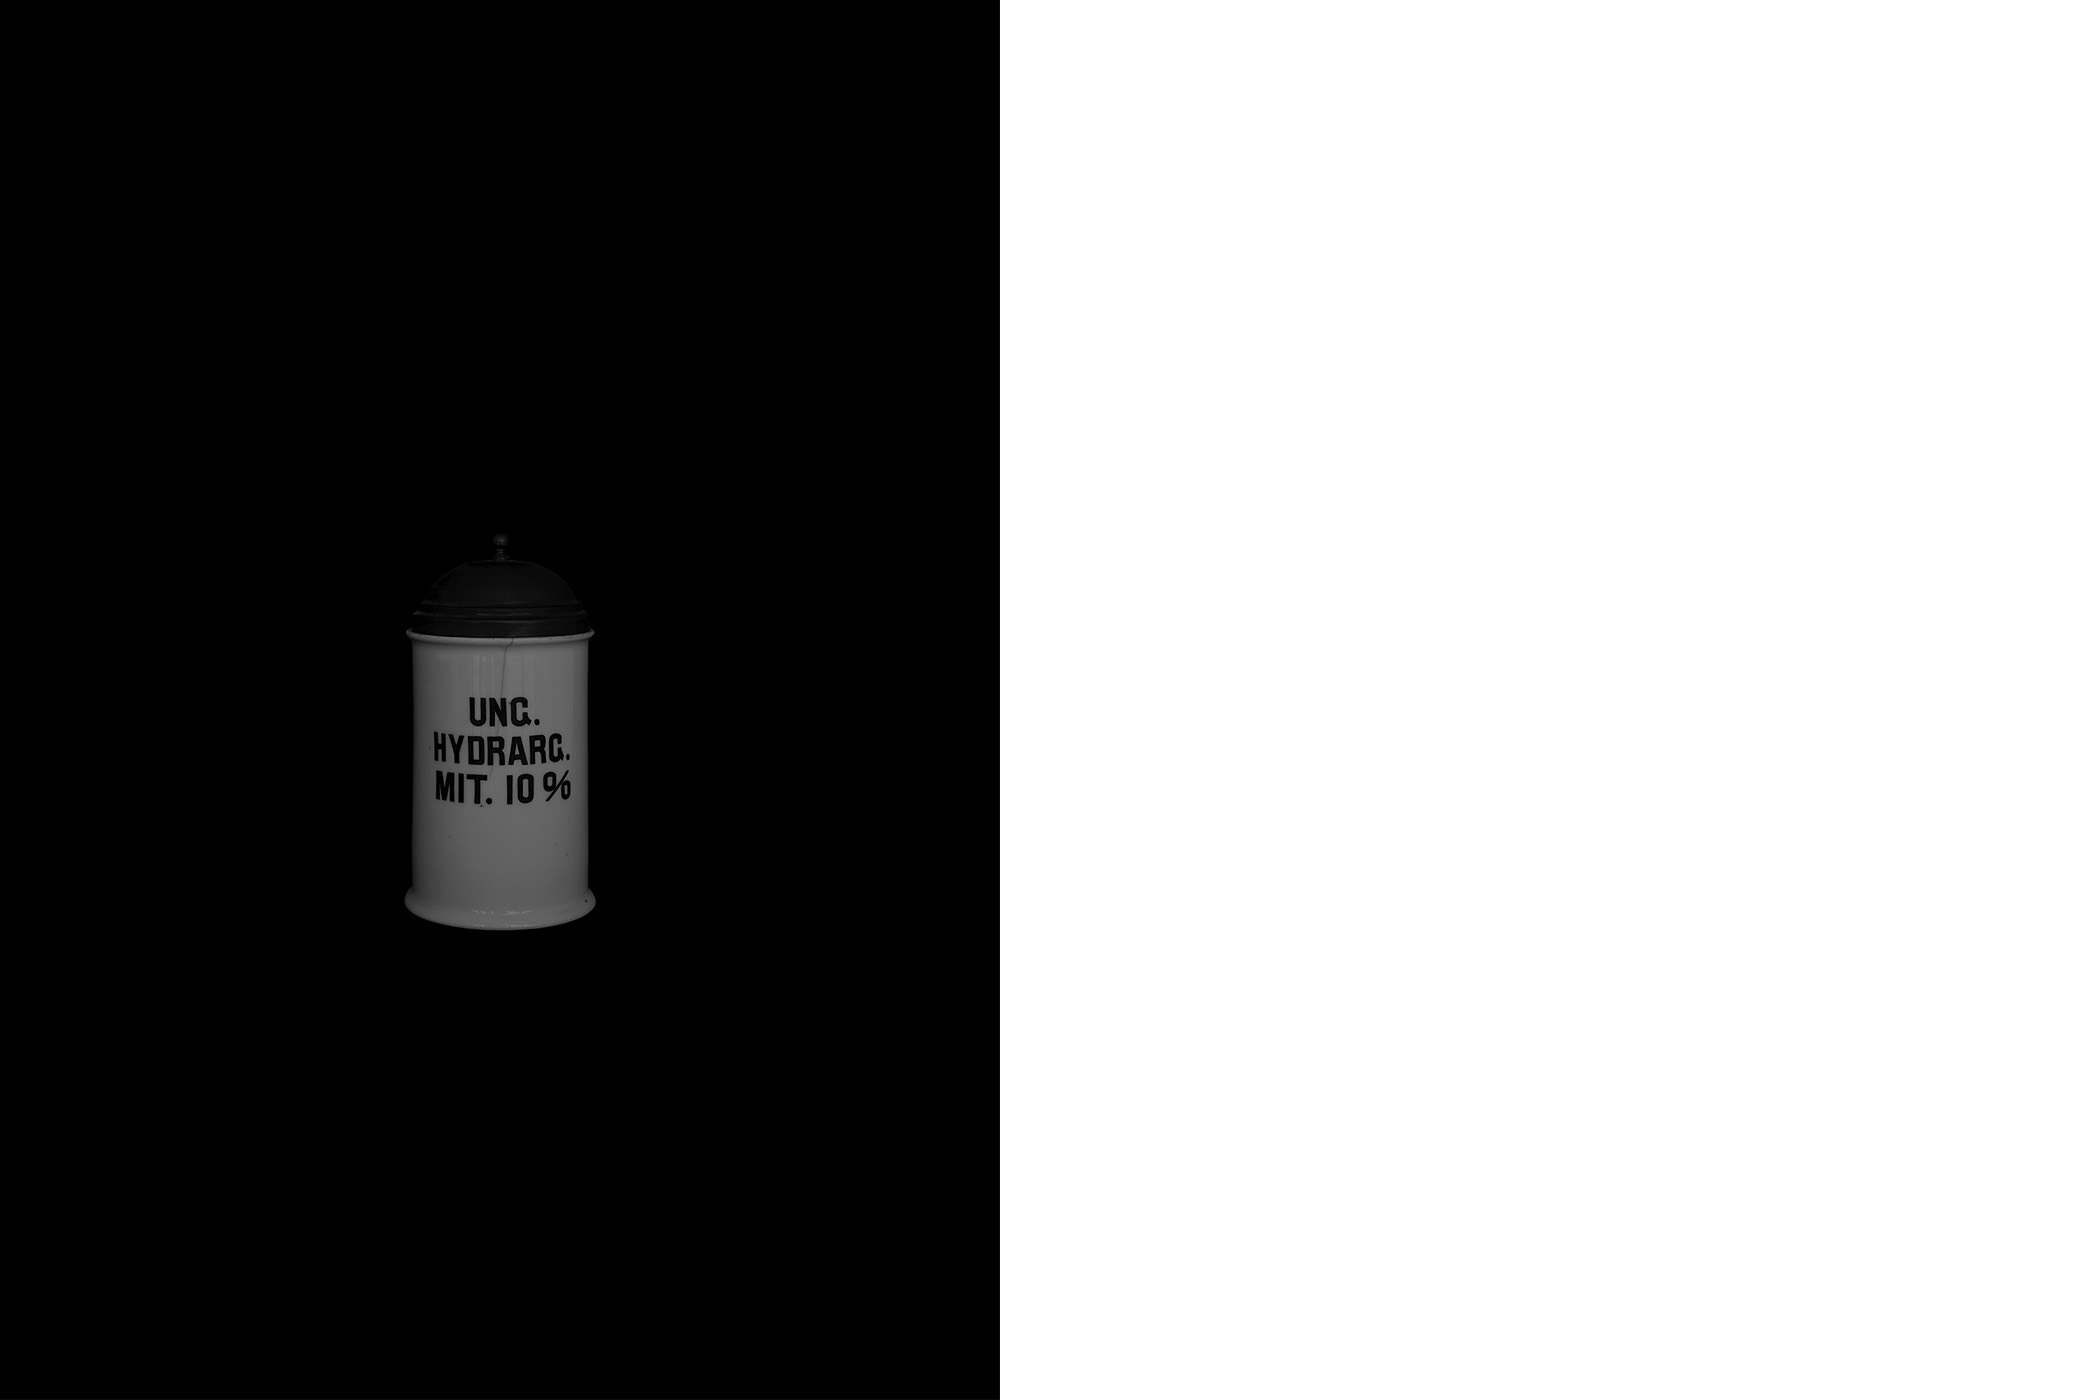

The first series draws from the collection of the Historical and Maritime Museum of Istria, featuring photographs of ceramic and glass apothecary jars transferred onto black paper using silkscreen printing. Instead of traditional ink, the prints were made with powdered active pharmaceutical substances, resulting in faint, almost ghostly images that echo the fragility and ephemerality of the source material.

The first series draws from the collection of the Historical and Maritime Museum of Istria, featuring photographs of ceramic and glass apothecary jars transferred onto black paper using silkscreen printing. Instead of traditional ink, the prints were made with powdered active pharmaceutical substances, resulting in faint, almost ghostly images that echo the fragility and ephemerality of the source material.

Untitled (Archive Pharmacy), 2024

screen printing on paper with color obtained from the powder of the active substances of medicines

graphic sheet 70 x 50 cm, framed 70,5 x 50,5 x 3,5 cm

1-20

Untitled (Archive Pharmacy), 2024

screen printing on paper with color obtained from the powder of the active substances of medicines

graphic sheet 70 x 50 cm, framed 70,5 x 50,5 x 3,5 cm